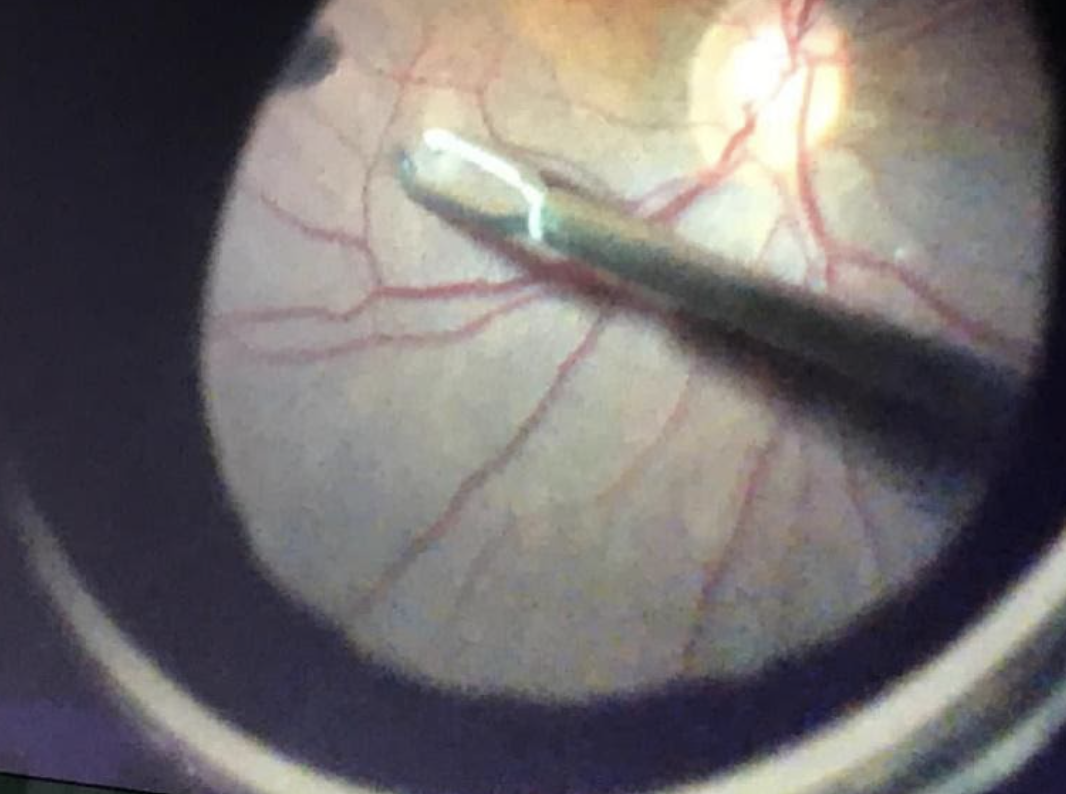

El tratamiento del agujero macular es quirúrgico. La cirugía a realizar se denomina: vitrectomía, pelado y gas.

El especialista realiza una vitrectomía, eliminando la capa más interna de la retina, llamada membrana limitante interna.